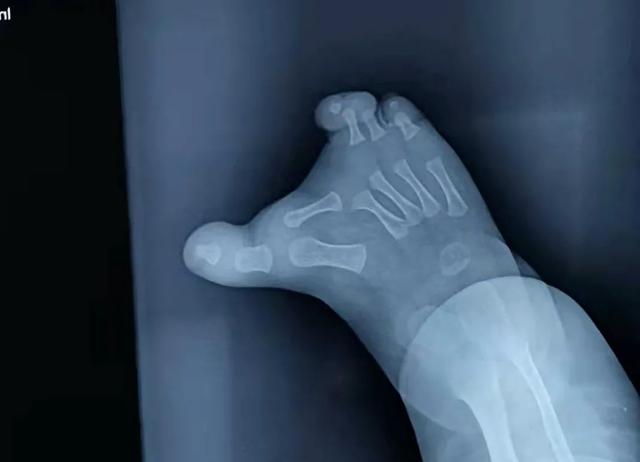

宝宝的脚是脚趾对脚趾的。通过x光,我们可以看到婴儿的第二个脚趾是水平生长的。这种情况要尽早治疗,因为第二个脚趾还在生长,时间越长,对其他脚趾的影响越大。